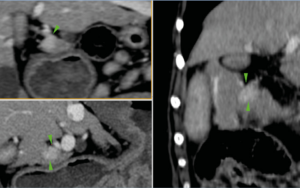

La tomografía computarizada (TC) puede ser particularmente útil en la investigación de insulinomas, puesto que el gas en el tracto gastrointestinal no supone una limitación y es una prueba más sensible en la identificación de pequeñas lesiones, aunque para ello se suele necesitar la TC de fase dual. El insulinoma se caracteriza por presentar una imagen de nódulo hipoatenuante con un gran refuerzo, únicamente en la fase arterial del estudio (halo de contraste alrededor del nódulo) y no en otras fases (imagen 1).

Imágenes 4A – 4K. Secuencia de imágenes quirúrgicas en un perro (con las imágenes del TC), durante una pancreatectomía total del lóbulo izquierdo y cuerpo del páncreas (usando la técnica de “guillotina” sutura/fractura con el nudo de Miller modificado) y resección de NNLL centinelas, por insulinoma en el cuerpo del páncreas.

Imágenes 5A – 5H. Secuencia de imágenes quirúrgicas en un perro (con las imágenes del TC), durante una pancreatectomía total del lóbulo derecho y parte del cuerpo del páncreas (usando la técnica de “guillotina” sutura/fractura con el nudo de Miller modificado) y resección de NNLL centinelas, por insulinoma en el lóbulo derecho del páncreas.